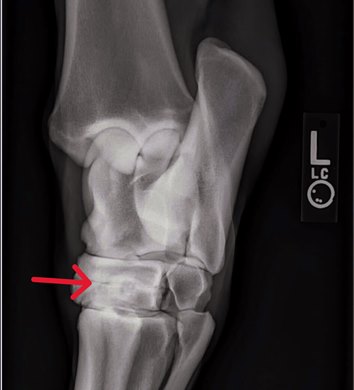

Abnormalities in the horse's hock (tarsus) are a common finding on radiographs. The hock is composed of several joints and is the equine equivalent of the human ankle. The hock is a hinge joint of the hind limb, which is crucial for shock absorption, weight-bearing, range of motion, and generating propulsion. The entire hock area is made up of joints, ligaments, tendons, and synovial fluid.

In the case of the Into Mischief colt, the horse had some degenerative changes in each hock in the distal intertarsal joint, the second joint up from the cannon bone.

"When I say degenerative changes, that is what some would commonly call arthritis, or arthritic changes which, eventually in many cases, leads to actual fusion of the DIT joint," Berk said. "The actual cause of this process is unknown."

Berk added this condition is something that develops over time and should not be confused with a condition known as "crushed hocks." Crushed hocks in foals, also known as cuboidal bone compression, occur when immature, soft cartilage (instead of fully formed bone) collapses under the foal's weight. Often caused by prematurity or excessive activity, this can lead to malformed hock joints and chronic lameness.

"In the case of distal intertarsal joint remodeling, these are normally formed tarsal bones," Berk said. "They're just exhibiting some degree of degenerative change in that particular joint."

The two lower hock joints (distal intertarsal and tarsometatarsal) account for very little of the hock's movement, according to Berk. In most cases, fusion of the joint does not adversely affect a racehorse's gait.